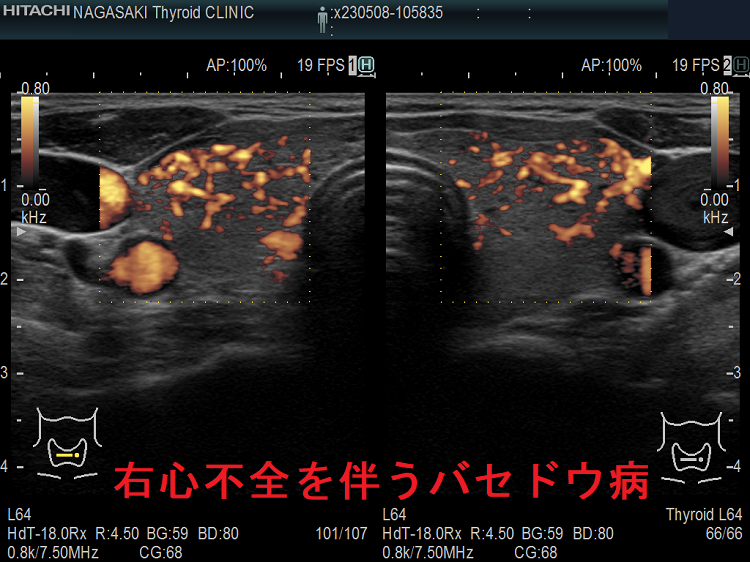

右心不全

甲状腺機能亢進症/バセドウ病の心不全は、右心不全が前景になり

- 循環血液量の増加で、予備力の少ない右心室は容量負荷・圧負荷を受けます。

- その結果、三尖弁輪が拡大し、三尖弁が閉じなくなります[三尖弁閉鎖不全症(TR)]→血液は右房に逆流し右房圧が上昇、静脈はうっ滞し頸静脈怒張・肝腫大・下肢浮腫が生じます(右心不全)。

- 甲状腺機能亢進症/バセドウ病の初期は左心室の障害に至らず、高い心拍出量は保たれているため、右心不全のみの状態(高心拍出性心不全)です。

[Methodist Debakey Cardiovasc J. 2017 Apr-Jun;13(2):60-63.][Clin Cardiol. 2000 Jun;23(6):402-8.]